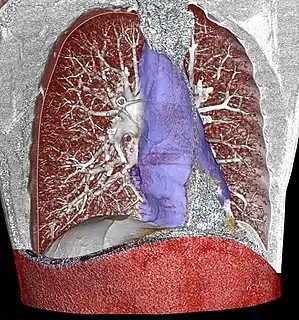

![]() 3D rendering of a high resolution computed tomography of the thorax, with mediastinum marked in blue. | |